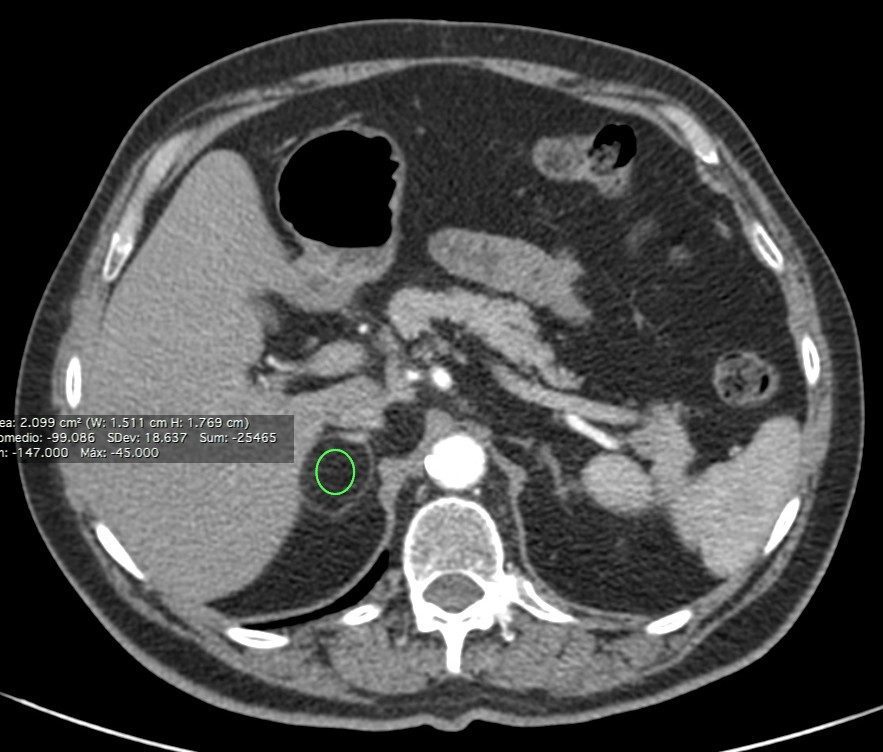

Paciente de 56 años en el que se descubre una masa suprarrenal derecha de 4,1 x 2.8 cm aprox., al realizar un TC de abdomen por otro motivo. Se procede al diagnóstico y caracterización de dicha lesión en la glándula suprarrenal derecha.

Calculamos la Fórmula WASHOUT, optaremos por la absoluta.

(PORTAL – TARDÍA / PORTAL – Sin CONTRASTE) x 100% = (54,8 – 12,1 / 54,8 – 2,08) x 100 = 80,7 %

El porcentaje de lavado es > 60%. Todos estos hallazgos establecen el diagnóstico de ADENOMA SUPRARRENAL.